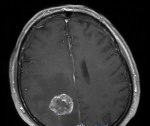

Рак мозга: симптомы, диагностика и лечение опухоли головного мозга

К сожалению, опухоли головного и спинного мозга встречаются сегодня не редко. Они составляют около 5% больных, у которых были обнаружены различные новообразования в организме. Причиной, способствующей развитию опухоли головного мозга, может быть черепно-мозговая травма, частое рентгеновское облучение головы, воздействие винилхлорида - газа, применяющегося при изготовлении изделий из пластмассы,